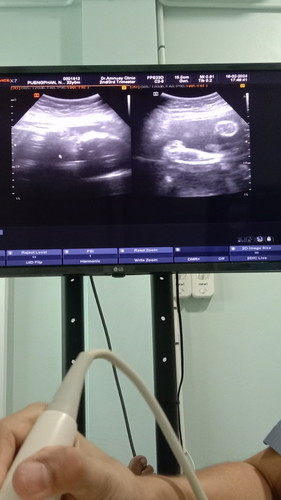

คำถาม เห็น เป็นผู้หญิงรึผู้ชาย

แม่เห็นเป็นผู้หญิงหรือผู้ชายค่ะ ท้องที่2 แอบหวัง อยากได้ลูกสาว คนแรกลูกชาย 😊

ภาพฝั่งขวาเป็นภาพขาน้องใช่ไหมคะ เห็นไม่ค่อยชัดเลย แต่ถ้าใช่ ตรงหว่างขาไม่มีจู๋งอกออกมา แปลว่าคุณแม่อาจจะท้องลูกสาวค่ะ